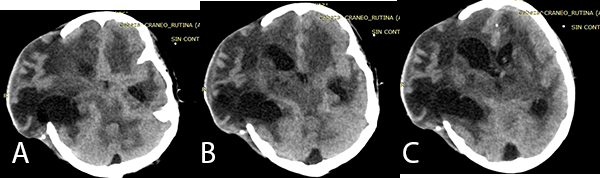

Posterior a la biopsia, el paciente presentó mayor alteración del sensorio, con TEM control evidenciándose hidrocefalia. Se decide la colocación de una Derivación Ventricular Externa (DVE) con medición de la Presión Intra Craneana (PIC) (Imagen 2).

Imagen 2: (A), (B) y (C) TEM cerebral sin contraste en corte axial muestra leve dilatación ventricular con catéter de DVE, además de ligera asimetría entre hemisferios cerebrales.

El paciente no presentó mejoría del estado de conciencia, ingresando a Unidad de Cuidados Intensivos donde se evidencia hipertensión endocraneana refractaria, con mediciones de PIC mayores de 20 mmHg sostenida más de 30 minutos pese a tratamiento neurointensivo. Debido a ligera asimetría interhemisférica (Imagen 2) con hipo densidades sugerentes de edema cerebral frontal derecho es sometido a una Craniectomía Descompresiva.

Posteriormente, el paciente persiste con deterioro clínico llegando a una escala de Vellore de IV(5) (en el examen físico presentaba signos de decorticación y pupilas anisocóricas); por falla de DVE se decide colocar un nuevo sistema de DVE, evidenciándose en la TEM control asimetría en los ventrículos (Imagen 3), motivo por el cual el paciente es sometido a una endoscopía para fenestración de septum pellucidum.

Imagen 3: (A), (B), (C) TEM cerebral sin contraste cortes axiales previa a la fenestración endoscópica, se evidencia hidrocefalia asimétrica post colocación de DVE en el cuerno frontal izquierdo.

En la TBC del SNC se evidencia que se produce una reacción inflamatoria afectando las cisternas basales con obliteración de las mismas, evidenciándose en la TEM cerebral como exudados isodensos o hiperdensos tal como indica Bathla et al.(10) En la TEM cerebral (Imagen 3) del paciente se evidenció que las cisternas basales se encontraban obliteradas por imágenes ligeramente hiperdensas.